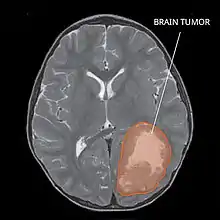

| Primitive neuroectodermal tumor of the central nervous system in a 5-year-old |

A central nervous system primitive neuroectodermal tumor, often abbreviated as PNET, supratentorial PNET, or CNS-PNET,[1] is one of the 3 types of embryonal central nervous system tumors (medulloblastoma, atypical teratoid rhabdoid tumor, and PNET).[2] It is considered an embryonal tumor because it arises from cells partially differentiated or still undifferentiated from birth.[1] Those cells are usually neuroepithelial cells,[1][2][3] stem cells destined to turn into glia or neurons.[4] It can occur anywhere within the spinal cord and cerebrum and can have multiple sites of origins, with a high probability of metastasis through cerebrospinal fluid (CSF).[1][2]